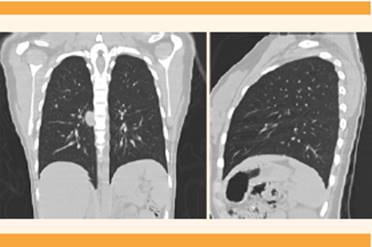

La TAC toracoabdominal encontró metástasis al pulmón y crecimientos ganglionares incluso de hasta 25 mm (Figura 2), motivo por el que se decidió enviarla al servicio de oncología pediátrica del Hospital Materno Infantil Toluca para tratamiento y donde continúa con seguimiento oncológico porque en nuestra unidad no se cuenta con ese servicio.

Los coriocarcinomas, por su gran capacidad de angioinvasión, que facilita su diseminación y propicia las metástasis pulmonares, cerebrales, hepáticas y a otros órganos, tienen metástasis temprana al pulmón incluso en 80% de los casos.11,12 En coincidencia con nuestro caso, en el que se diagnosticó metástasis pulmonar con base en los estudios de extensión, confirma la gran invasión vascular de este tumor.